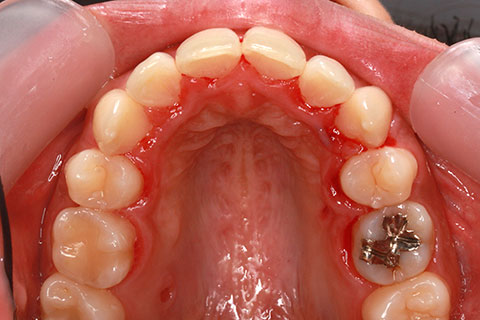

矯正期間24ヶ月

ハーフリンガル矯正4(上の歯のみ舌側矯正で治療)

治療前

治療中

治療後

- 年齢・性別

- 23歳女性

- 治療期間

- 2年0ヶ月

- 抜歯

- 上下4番抜歯

- 治療費

- 110万円

- 備考

- マルチブラケットを用いた矯正治療

- 治療内容

- 施術の副作用(リスク)

- 表側矯正と比較して、前歯のラビッティング(舌側傾斜)を起こしやすい。